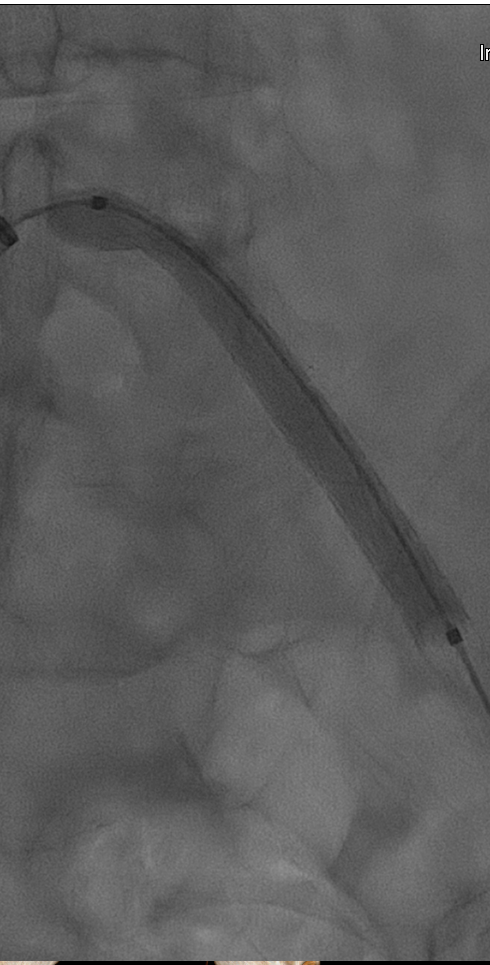

术前造影显示左髂总动脉起始部闭塞,支撑导管辅助翻山成功后,用4X150mm,6X150mm球囊分别做预扩。

(术前造影及4x150mm球囊预扩)

(6x150mm球囊预扩)